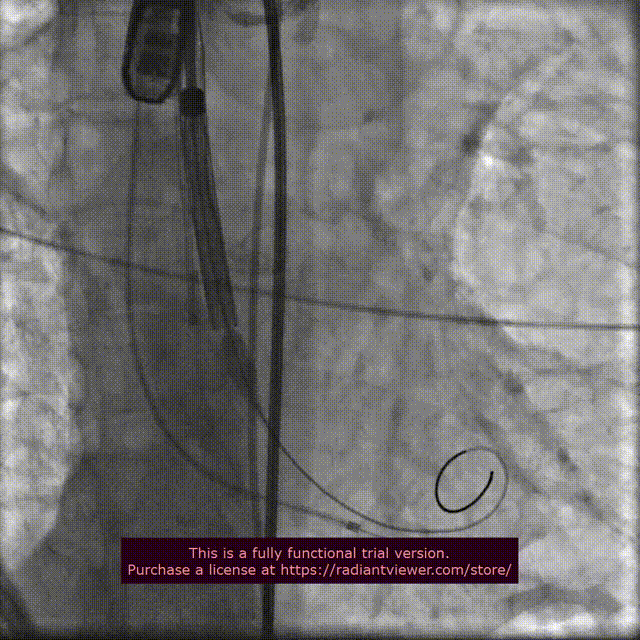

手术过程概览:

行主动脉根部造影后,直头导丝成功跨瓣,选择左冠切线位进行球囊预扩;TaurusElite AV23瓣膜送至主动脉弓,主动脉根部再次造影,并取零位释放位置。

球 囊 预 扩

瓣膜精准定位

在团队的密切合作下,瓣膜释放到工作位,行主动脉根部造影评估,明确定位良好,瓣膜缓慢释放,瓣架依次稳定脱钩,花冠完全展开。

释放到工作位

瓣膜缓慢释放,稳定脱钩